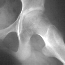

XRAYS

A CT scan in August showed joint effusion which was aspirated and evaluated.

The aspirate was negative for infection or other pathology.

An arthrogram performed was also negative. Both studies done at outside

facilities.

Recent radiographic findings revealed the following: Bone scan with

increased uptake left hip on both sides of joint

.

Joint space narrowing left hip to 2 mm

- Hallmark is narrowing of the joint space from normal 3-5 mm to values

<3 mm.

- Associated osteopenia of the periarticular osseous structures

- Irregular blurring of subchondral sclerotic lines

- Enlargement of the fovea capitis femori

- With time, can develop mild coxa magna and femoral neck widening and

frequently a premature closure of the proximal femoral physis and trochanteric

apophysis.

- Mild protrusion and a lateral buttressing osteophyte at the acetabulum

- Limited area of periosteal new bone formation along inferior femoral

neck

RADIOGRAPHIC TESTS INCLUDE

- Arthrography - help document cartilage resorption and joint space narrowing

- Bone scan shows increased uptake on both sides of joint

- CT Pelvis - document subchondral bone changes, cartilage resorption,

and narrowing of joint space

- MRI - may be of benefit, but there is no large volume of experience

using MRI found in the literature